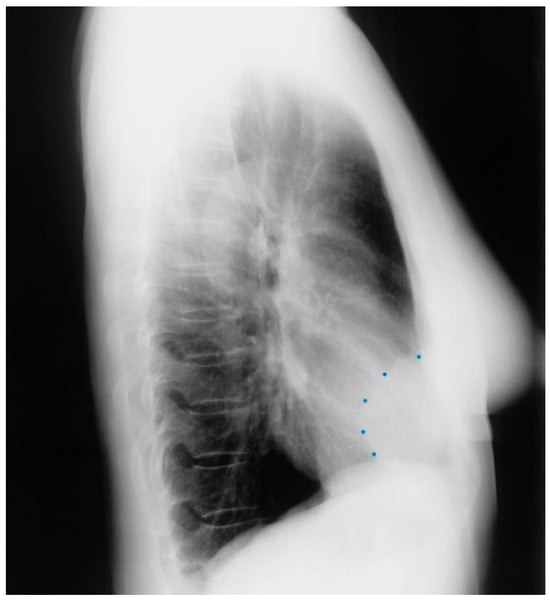

Figure 24.

Lateral chest X-ray in an adult with previously operated tetralogy of Fallot (toF) above: This X-ray shows sternal wires from a previous median sternotomy. The retrosternal airspace is mildly occupied by right ventricular enlargement. There is a metallic surgical clip in the upper middle mediastinum from one of her previous surgical procedures. Doppler echocardiography revealed severe pulmonary valve regurgitation, moderate–severe tricuspid regurgitation, moderate–severe right ventricular dilation and dysfunction. The patient subsequently underwent pulmonary valve replacement and tricuspid valve repair.